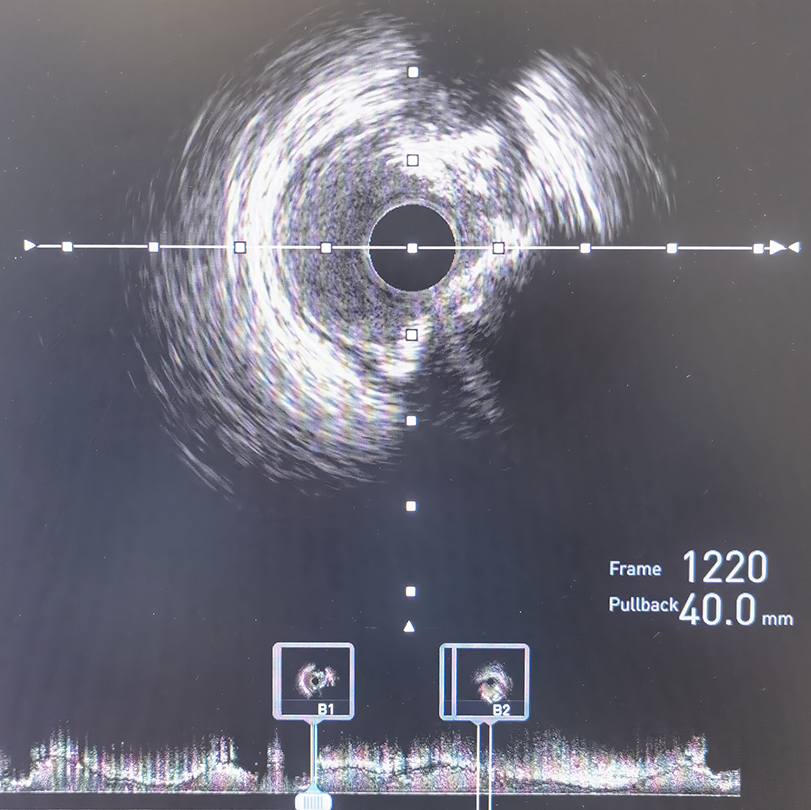

冠脉造影及IVUS检查提示前降支重度狭窄伴严重钙化